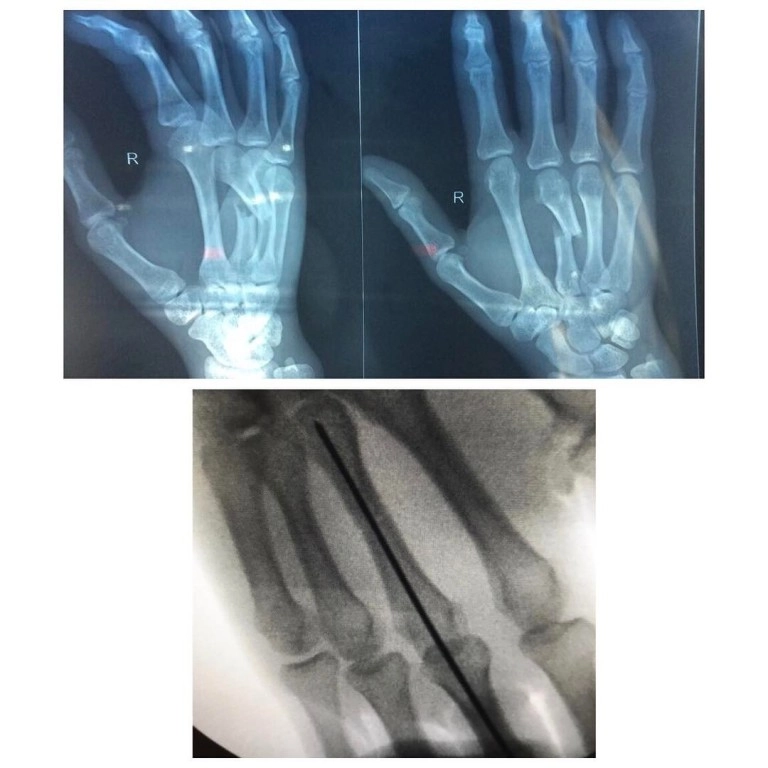

– Врач также ведет направление "Кистевая хирургия",

где успешно решает вопросы, связанные с повреждениями

и заболеваниями кисти. Для восстановления после травм